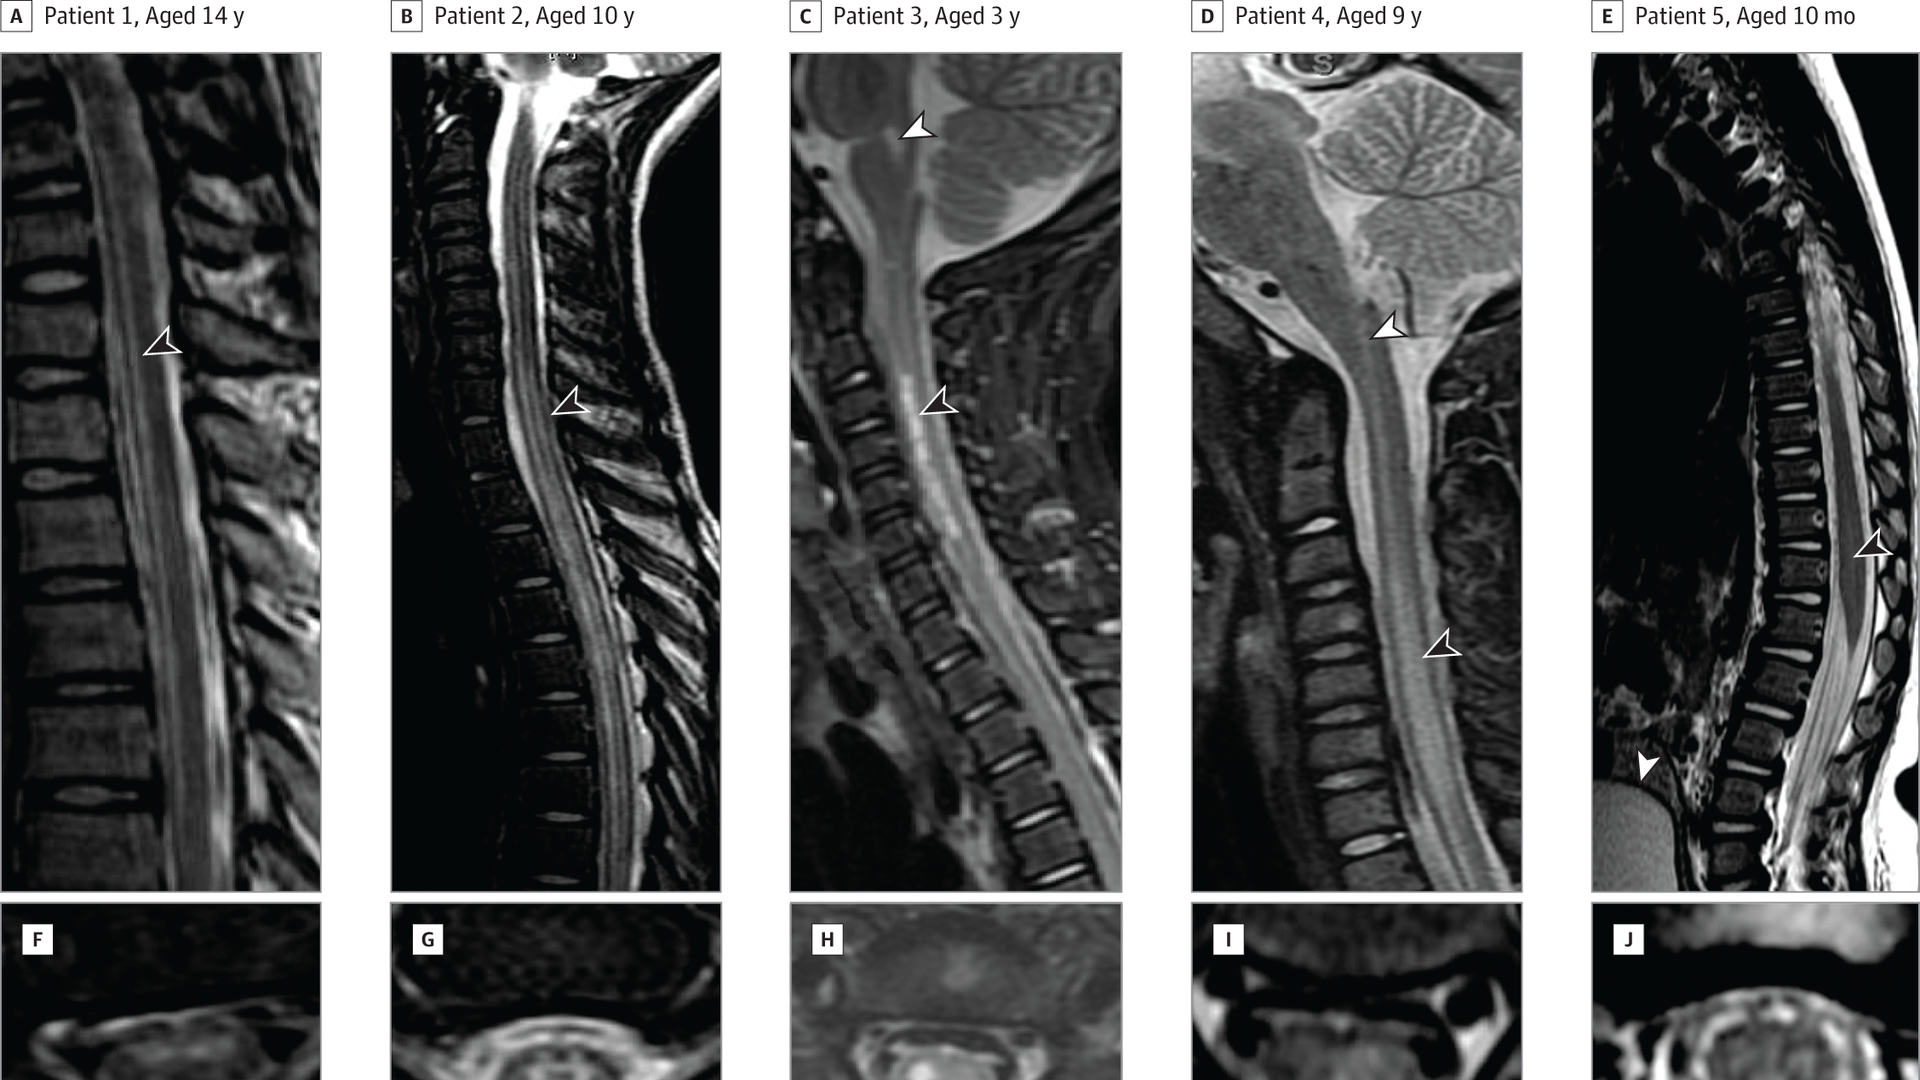

MRI of spinal cords from 5 AFM patients. Photo: Van Haren K, Ayscue P, Waubant E, et al. Acute Flaccid Myelitis of Unknown Etiology in California, 2012-2015. JAMA